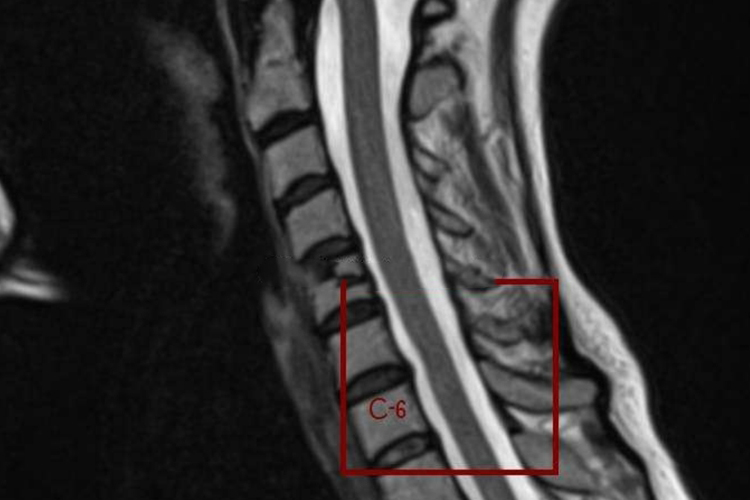

颈椎膨出,即颈椎间盘膨出,是指颈椎间盘的纤维环部分或全部破裂,髓核向外膨出,但尚未突破纤维环而压迫神经根或脊髓的现象。当长期不良姿势等因素导致这一现象发生在颈椎的第3、4、5、6、7节时,可能会引发颈部疼痛、僵硬、活动受限,甚至放射至肩背部和上肢的疼痛、麻木等症状。